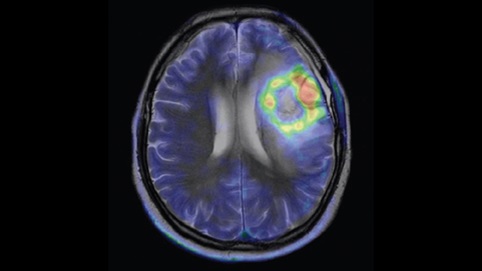

核医学

核医学是放射性同位素在医学领域的应用。它集合了核技术、电子技术、计算机技术、化学、物理和生物学等现代科学技术,是放射诊疗的重要组成部分。核医学诊疗方法不仅在疾病的诊断和治疗中能发挥重要作用,而且也是重要的医学研究手段。通常新药在试用于临床之前,都要用放射性同位素加以标记,以研究药物代谢的规律。

PET脑显像